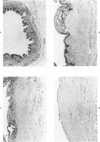

Common biliary ducts of 32 adult mongrel dogs were ligated for a period of 2 days to 6 weeks. Sham-operated animals served as controls. Bile ducts were removed at sacrifice, and biophysical, morphologic, and biochemical parameters were measured. Our study shows that biliary duct ligation results in an immediate increase of intraductular pressure and is followed quickly by significant increase in the rate of collagen synthesis and the activity of prolyl hydroxylase. Histologic data show subepithelial inflammation followed by marked increases in periductular fibrosis. This fibroproliferative response is paralleled by peak levels of prolyl hydroxylase activity at 2 weeks prostligation. Paradoxically, bile ducts continuously distend throughout the ligation period despite increased fibroplasia. We present here the first topographic (SEM) study of normal and ligated common bile duct epithelium. Following 2 weeks of ligation large crater-like fenestrae are seen ductular epithelial surfaces. This is followed by focal epithelial sloughing. We speculate that the continuous distention and epithelial necrosis seen in the present study may be due to biliary stasis and/or subepithelial infiltration of bile through epithelial fenestrae. This hypothesis is supported by our studies which show that collagen extractibility is markedly increased by the addition of bile to the homogenate.